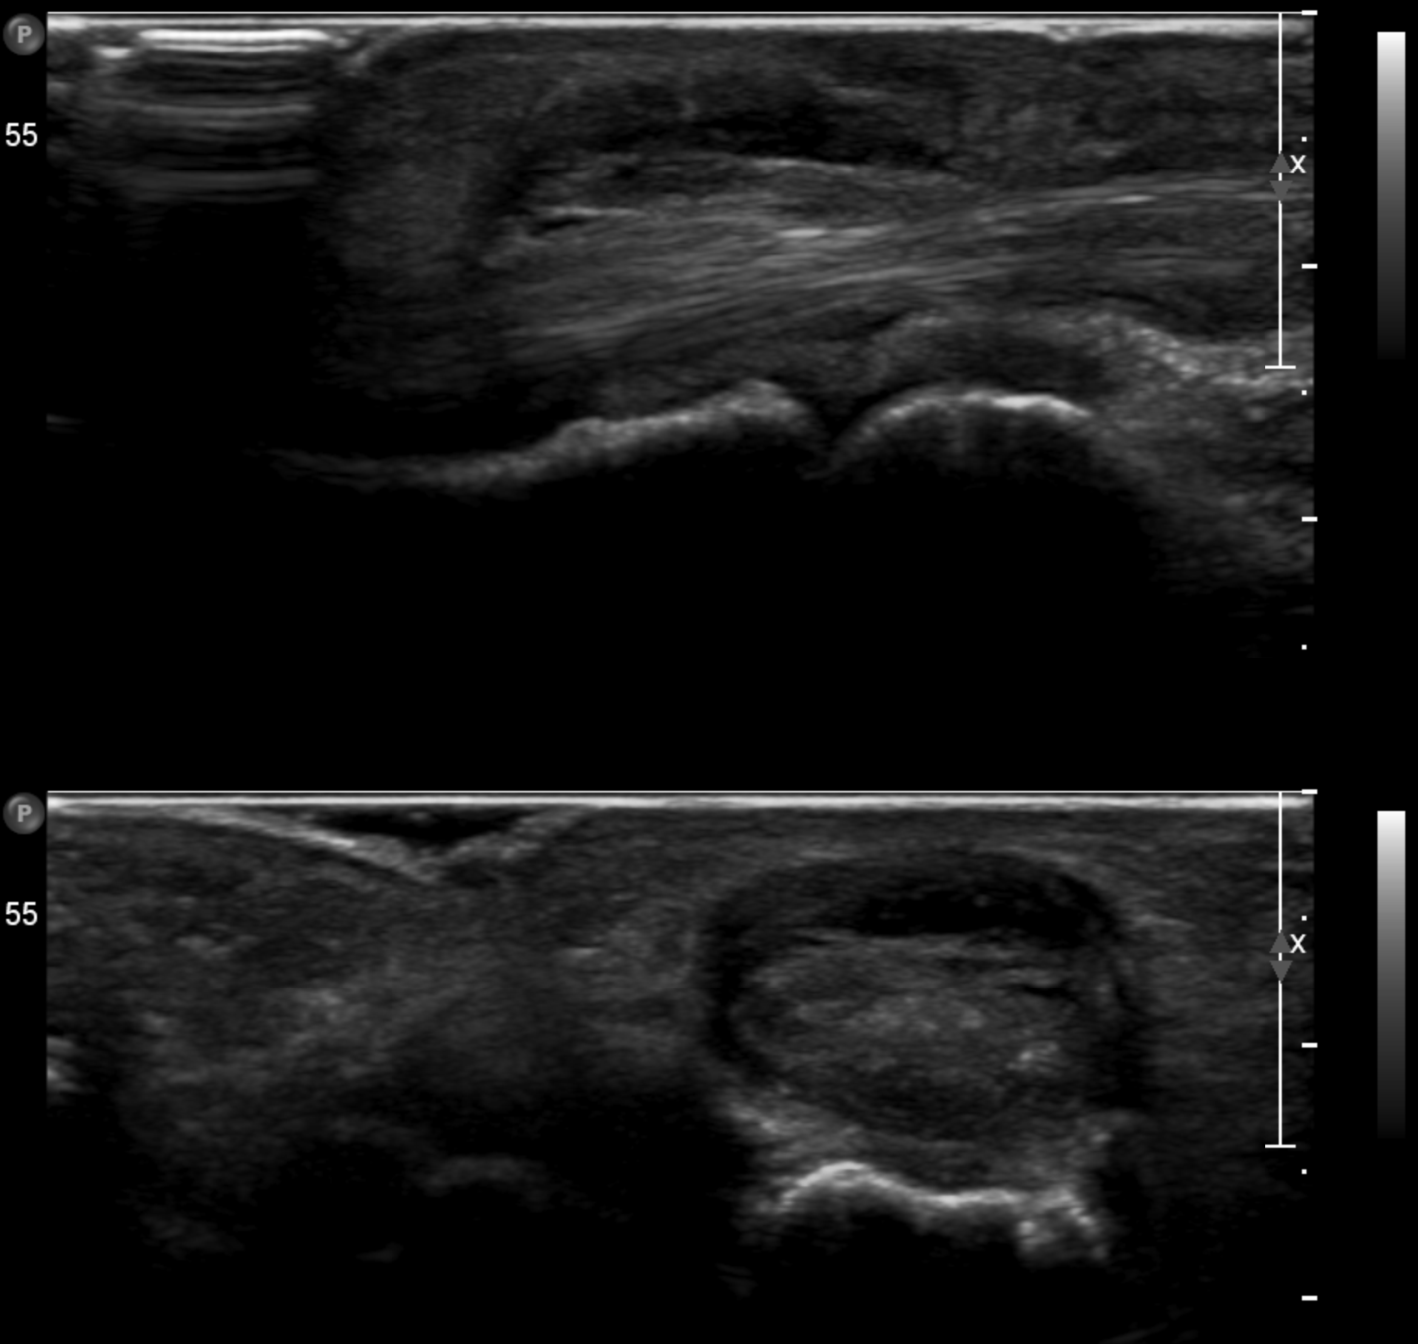

Trigger finger Szerző: admin | szept 4, 2015 | Ligamentous injury, MSK, Small joints | Nincsenek hozzászólások USS Sag & Axi at the level of the MCP joint: Gross thickening of the A1 pulley of fourth flexor tendon on the right without vascularity consistent with the trigger finger symptoms.